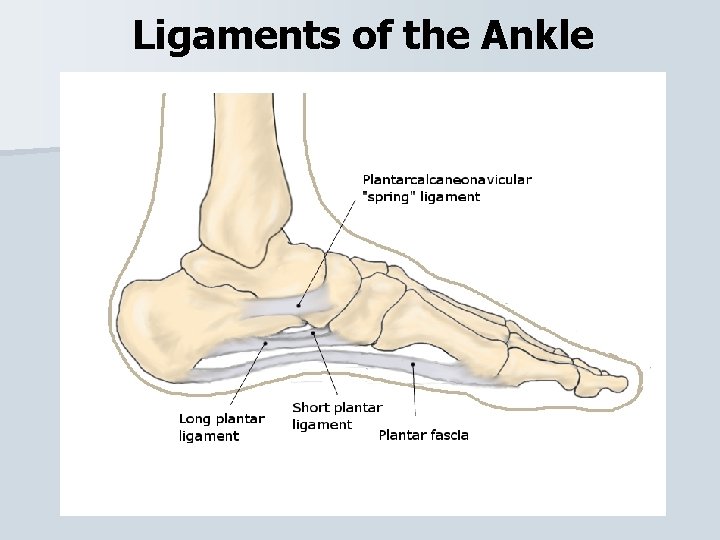

Ligaments of the Ankle

Ligaments of the Ankle

Ligament Injuries Arch Sprain An arch sprain can be caused by running on a hard surface, wearing improper footwear, or repetitive stress. • The athlete will report pain over the involved arch except the metatarsal arch will cause pain at the ball of the foot. • PRICES, strengthening and arch support. •

Ligament Injuries Plantar Fasciitis • The plantar surface of the foot has a thick layer of fascia that becomes injured from chronic stress. • It begins with tenderness at the bottom of the calcaneus and progresses to the toes. • Some cases the plantar fascia pulls on the calcaneus and causes a heel spur.